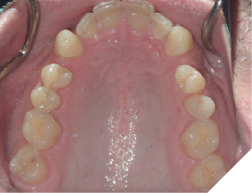

Fig. 2A

Fig. 2B

Fig. 2C

The majority of the orthodontic practices offer a period of “supervised retention” to their patients and communicates the customized retention recommendation with the patient’s general dentists. It is extremely important to work as a team to achieve long term clinical success in maintaining a functional bite and aesthetic smile. The general dentists continue to see their patients on a regular basis and have an opportunity to assess the orthodontic retainers and the bite after the supervised retention period is completed by the orthodontists. With great care, orthodontic retainers would serve for a long time (Fig. 1) without any major issues. However, in some cases, the failure to notice the clinical problems early on results in functional issues that would require a comprehensive orthodontic treatment to correct it (Fig. 2).